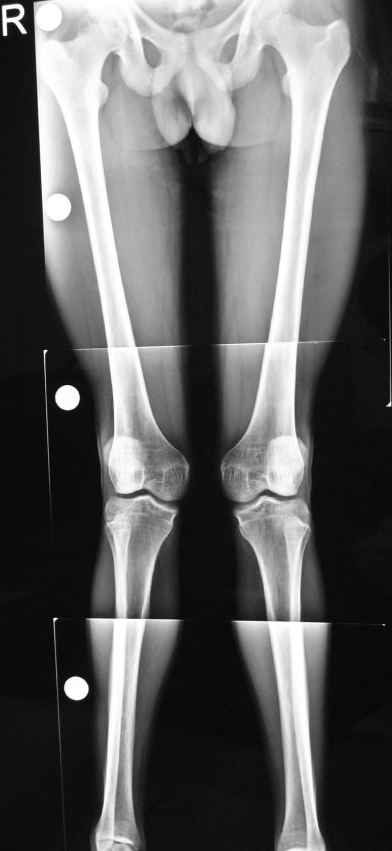

hello sirs, he is a 21 year old male short heighted thin built with failed conservative treatment tried for ? post rcketic deformity in childhood and teenage with bilateral genu valgum with intermalleolar distance 14cm and no flat foot,

the deformity is in the femur as it fully corrects on flexion of the knee his main complaint is that his knee knocks while walkingand pain in both knees while walking

my question here is 1. which correction is more reliable a medial closed wedge or a lateral opening wedge osteotomy with bone graft

2. if medial then what implant and if lateral then what implant ?

my plan is to do a lateral opening wedge osteotomy with bone graft but i am a little confused about the implant (lower end femur locking plate or some other implant)